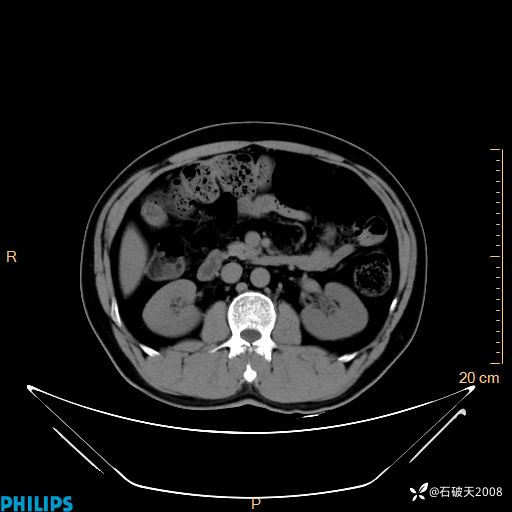

MIP